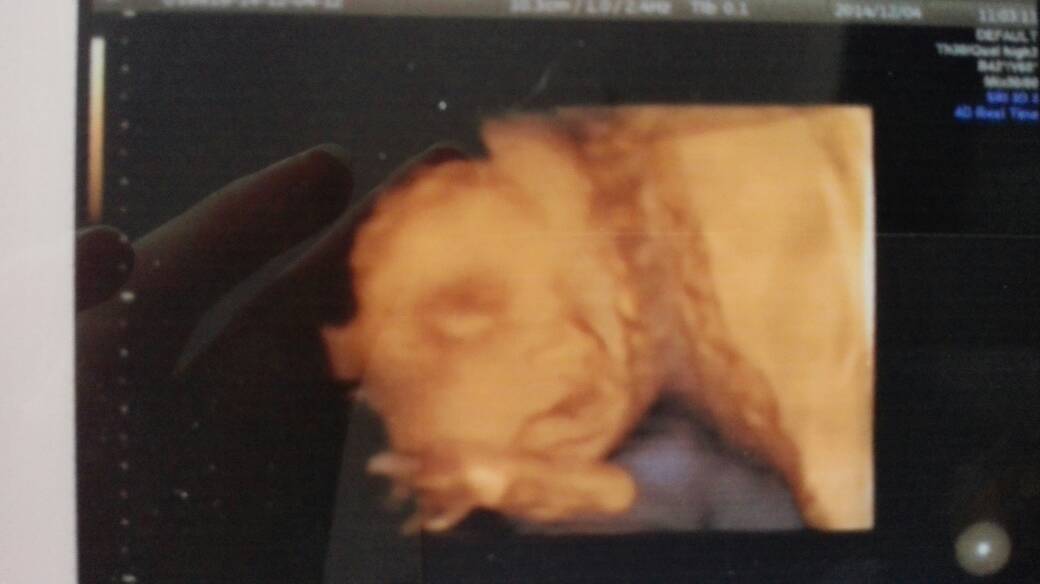

有没有已经做了四维彩超的亲啊?今天和老公一起去照四维,就给我照了两张面部的照片,四肢啊耳朵啊什么的都不知道长啥样子,在我前面的一个孕妇七个月了医生照的非常详细,这是为什么啊?医生不负责嘛?

你好,这个情况不能说一声不负责的,照几张图并不重要,重要的是下面的文字描述,只要文字描述了胎宝宝的四肢、耳朵等处,并且描述的是正常的,那就代表胎宝宝的这些地方没有毛病,是正常的。如果看不清楚,医生会写明看不清楚。

我的有四张。不过都没有下半身。

嗯嗯,一共两张,另一张是动脉血流的